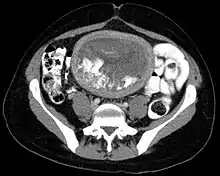

The diagnosis is strongly suggested by ultrasound (sonogram), but definitive diagnosis requires histopathological examination. On ultrasound, the mole resembles a bunch of grapes ("cluster of grapes" or "honeycombed uterus" or "snow-storm").[14] There is increased trophoblast proliferation and enlarging of the chorionic villi, and angiogenesis in the trophoblasts is impaired.[15]